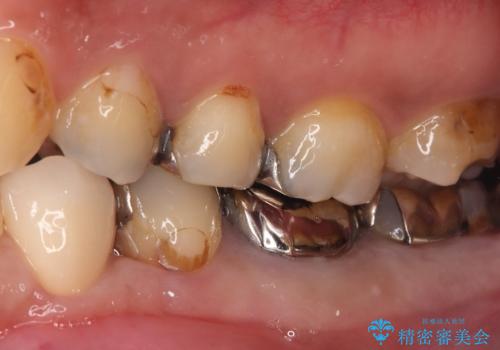

- 左下4番の奥歯に、歯肉の下まで進行した深い虫歯を認め来院されました。通常であれば神経を抜く必要があるほど深い虫歯でしたが、患者様の歯をできる限り保存するため、歯の神経を抜かずに残すことを目指す治療計画を立案。歯肉の下にある虫歯を適切に治療するため、歯周外科処置で歯肉のラインを調整した上で、精密なセラミッククラウンで修復することになりました。

まず、虫歯を徹底的に除去するために、歯周外科処置で歯肉のラインを調整し、治療部位を露出させました。その後、神経に近接した深い虫歯を慎重に除去。神経の保護処置を施し、歯の神経を抜くことなく保存することができました。型取りから、患者様の歯の色や形に合わせたオーダーメイドのセラミッククラウンを作製。最終的に、精度の高いクラウンを装着し、咬み合わせを細かく調整しました。これにより、神経を温存しながら、虫歯の再発を防ぎ、快適な咬み心地を取り戻していただけました。